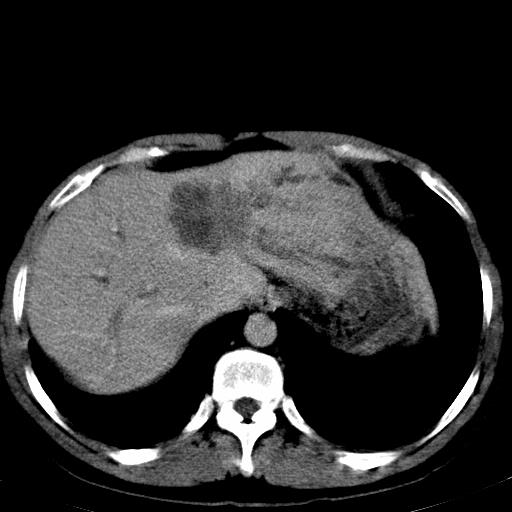

患者上腹部疼痛一月余,伴巩膜黄染;

考虑肝左叶胆管细胞癌侵犯肝门区并肝内胆管及肝总管扩张。

肝左叶肿块清度增强,所在的叶胆管扩张。考虑胆管细胞癌。

肝左叶胆管细胞癌侵犯肝门区并肝内胆管及肝总管扩张

考虑肝左叶胆管细胞癌侵犯肝门区并肝内胆管及肝总管扩张、肝门淋巴结肿大。